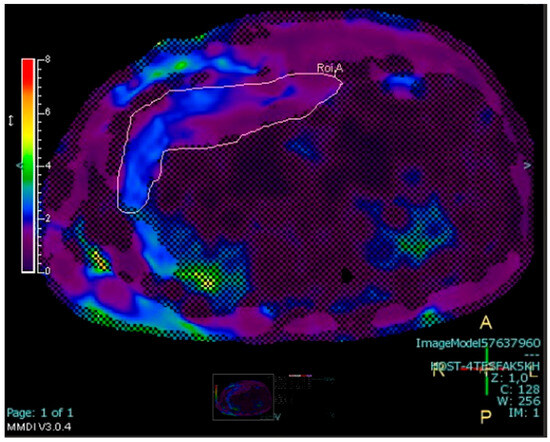

2.4.3. Measurement of Abdominal Fat Stores